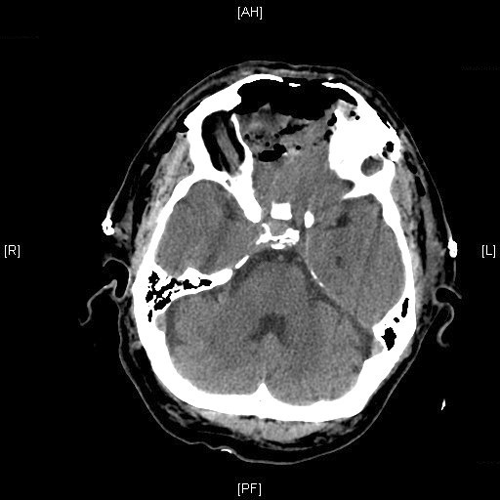

Clinical informationThe patient was a 54 year-old man who came to our clinic with the chief complain of a swelling between his eyes for 18 months. He reported frequent headache, changes in vision including double vision and decreased ability to smell. There was also minor changes in taste and dizziness but he did not report any syncope events. Physical examination revealed widening of nasal bridge and hypertelorism. His facial expression, motility, and strength are preserved. The pupils are equal, round and reactive to light. A CT scan and MRI was performed and demonstrated a large cystic mass as illustrated below. A biopsy was performed through the nasal cavity which yielded small fragments of spindle cell neoplasm with no high grade features demonstrated. Based on the biopsy result, the mass was excised and yielded the following representative images.

Radiologic Images of the Case: CT scan demonstrated a large midline mixed density mass with fat density that occupies the ethmoid sinus with extension through the cribiform plate into the inferior portion of the anterior cranial fossa. The mass is 5.1 x 3.2 cm in greatest dimension (Panel A). Bone windows of CT scan demonstrated bone expansion suggestive of remodeling (Panel B). On MRI, spoiled gradient recalled (SPGR ) post contrast images showing mass is either avidly enhancing or bright on T1 precontrast. (Panel C). The mass hypointense signal intensity compared to brain parenchyma with surrounding areas of increased signal (suggestive of entrapped mucus) on T2 weighted images (Panel D and E).